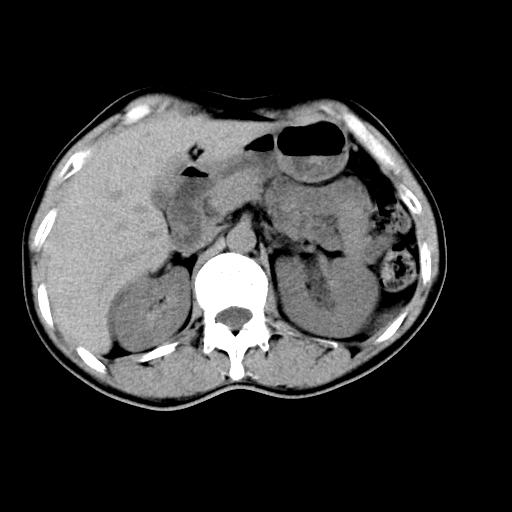

男,47岁,左输尿管结石碎石治疗后10余日。彩超示:左输尿管下段狭窄、输尿管积水。请各位讨论一下左输尿管下段结石还是静脉石?

两侧髂总动脉壁斑状及点状钙化.左侧输尿管行经与左髂总动脉相交后见高密度影,且下段输尿管管腔未见扩张,应该要考虑结石伴以上输尿管及肾盂积水.但右侧结节状高密度影,也应该是结石吧!那以上输尿管未见扩张呢!因此静脉结石可能性也较大.请问楼主碎石前左侧输尿管结石位置.

左侧输尿管有轻度扩张伴有肾盂积水,输尿管下段周围的高密度影不象在输尿管内。

同意,不支持结石。(因显示该高密度影前见扩张输尿管影,另外两侧对称显示)。

左侧高密度影在左侧输尿管的内侧方,所以不考虑输尿管结石.

我认为不是结石的可能性大,因为他的位置和血管钙化的位置邻近